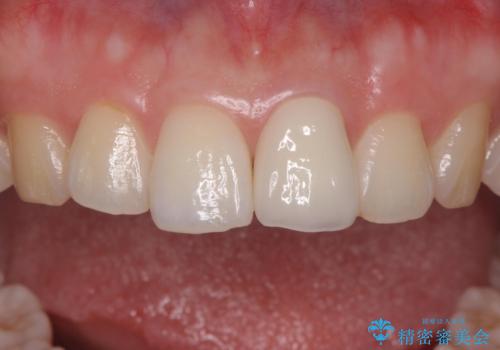

前歯の変色とガタつき ジルコニアクラウンでの修復

- 前歯の変色とガタつきが気になるとのことで来院された患者様です。

根管治療からやり直しを行った後、ジルコニアクラウンで修復することで、ガタつきと変色の両方を改善していきます。

ガタつきと変色の両方を改善することができ、大変喜んでいただけました。

少しのガタつきであれば、矯正治療を行わなくても改善できる場合があります。